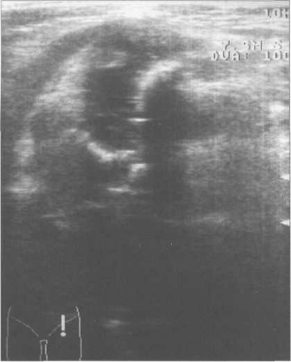

При исследовании в поперечной плоскости ногу сгибают под углом примерно 90°. Датчик устанавливают в проекции вертлужнои впадины и головки бедра. Получают срез шейки и головки бедренной кости, а также седалищной кости. Гипоэхогенная головка бедренной кости при этом сканировании в норме оказывается полностью погруженной между метафизом спереди и подвздошной костью сзади, образующими латинскую букву U (см. рис. 19.88). Гипоэхогенная головка бедра при этом расположена как бы внутри.

Рис. 19.88. УЗИ тазобедренных суставов в положении сгибания в аксиальной плоскости, получение «U» схемы.